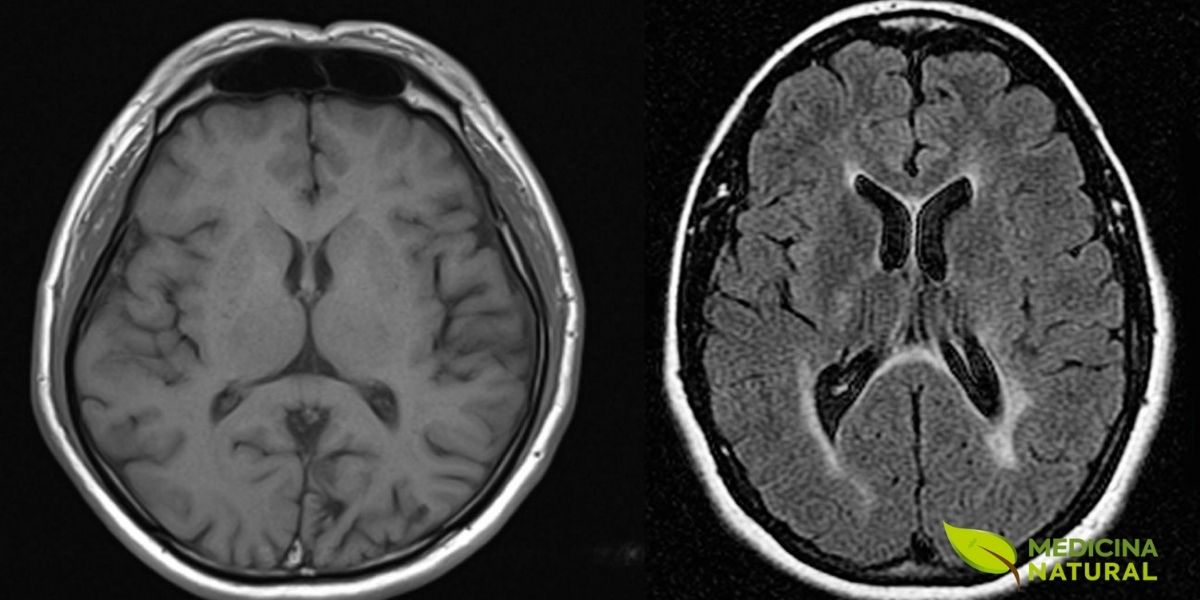

Uma Nova Esperança para a Esclerose Múltipla

A esclerose múltipla afeta o sistema nervoso central, causando danos à bainha de mielina. O dimetilfumarato, derivado do ácido fumárico, foi aprovado como tratamento oral eficaz para formas recorrentes desta doença neurológica debilitante. Exames de ressonância magnética são fundamentais para monitorar a progressão da esclerose múltipla. Estudos clínicos demonstraram que o tratamento com dimetilfumarato reduz significativamente o número de novas lesões cerebrais visíveis nestes exames.

Estudos DEFINE e CONFIRM

A aprovação do DMF pela FDA dos EUA em 2013 marcou um ponto de virada significativo. A eficácia foi estabelecida em dois grandes ensaios clínicos de fase 3. Foram o DEFINE e o CONFIRM. Esses estudos demonstraram que o tratamento com DMF reduziu a taxa anual de surtos em aproximadamente 50%. Também retardou a progressão da incapacidade física.